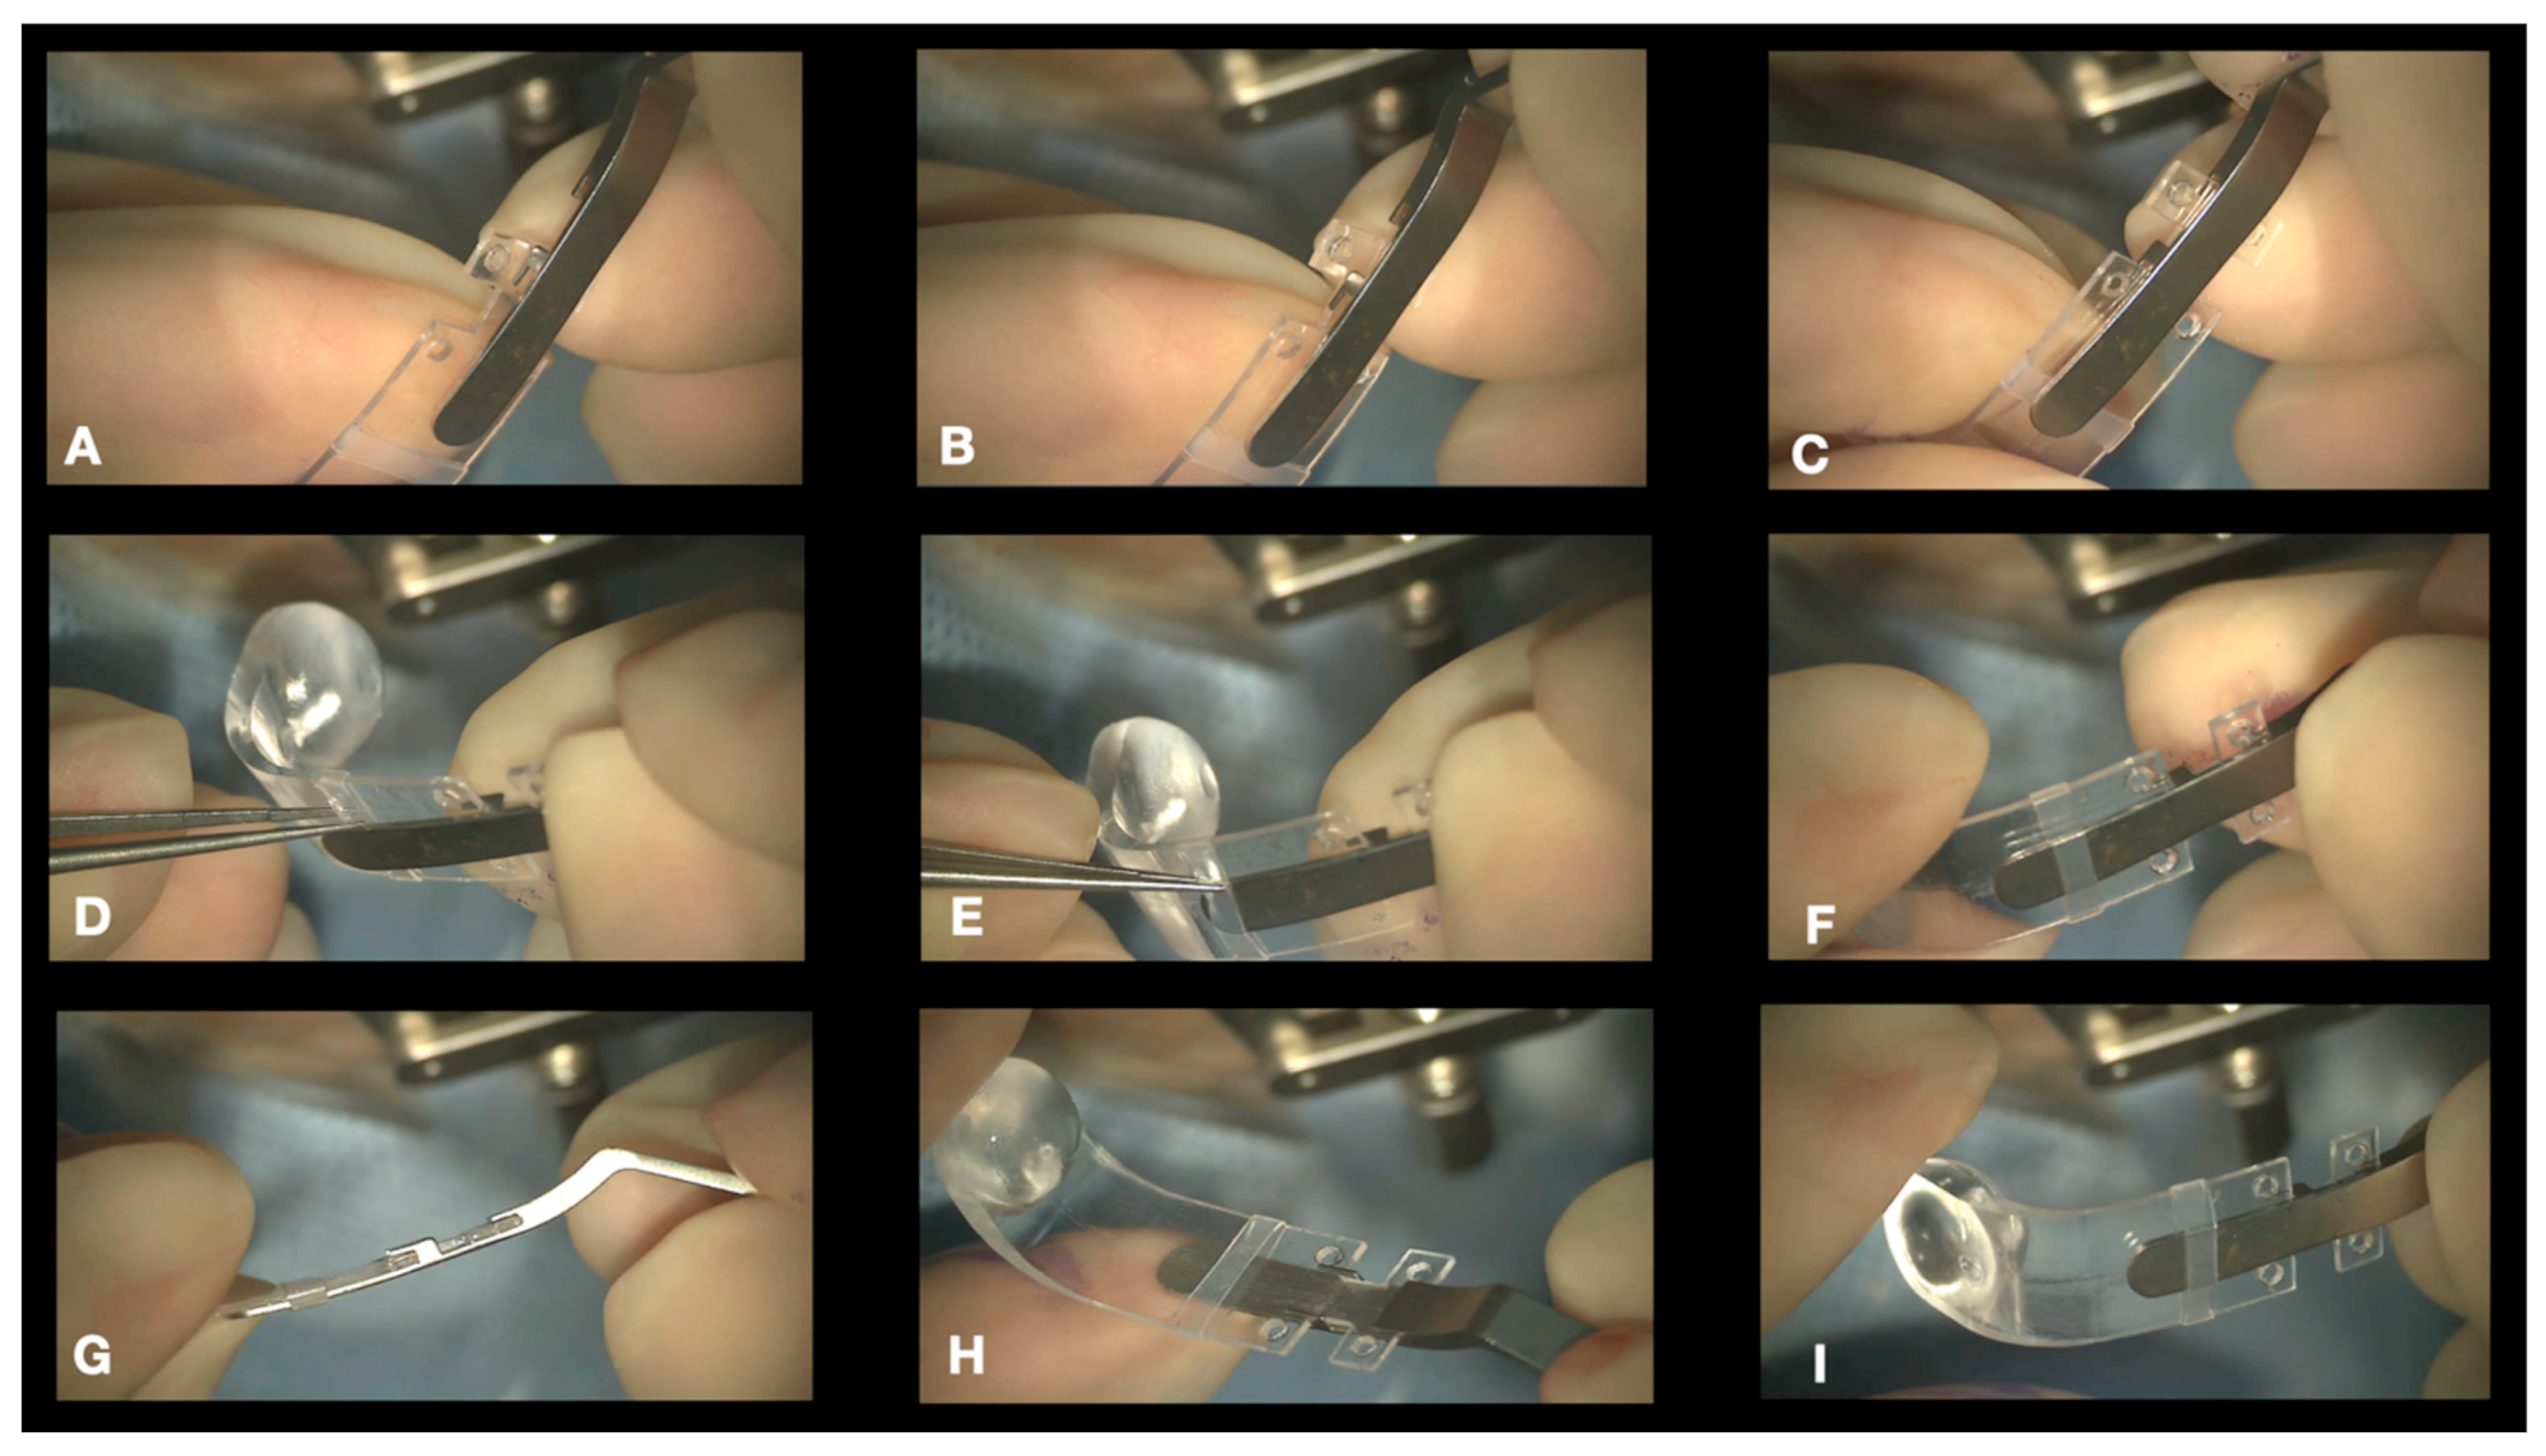

- Connecting the NPB on the NPD Loading device. We suggest connecting the NPB to the NPB loading device (Figure 6). As an alternative, the NPB can be held with bayoneted forceps, but attention should be taken not to break the NPB. To connect the NPB to the NPB loading device, it is necessary to execute the following steps:

- Hold the handle of the NPB loading device.

- Align the tip of the loading device to the external side of the NPB arm.

- Insert the tip of the loading device into the silicone sleeve with the help of non-toothed forceps.

- Connect the teeth of the loading device, embracing the NPB anterior wings.

- Connecting the Illuminated Fiber to the NPB. A 25-, 27-, or 29-gauge illuminated fiber can be slid onto the external side of the arm through the silicone sleeve and finally inserted into a dedicated lodge under the head of the NPB (Figure 2b and Figure 7). The light helps with the transillumination function, but we observed that surgery can be performed without any light and using only the microscope view.

- Insertion of the NPB. The NPB is inserted into the superotemporal quadrant by gently sliding and pushing the head, with a rotational movement, first along the eyewall and finally toward and behind the posterior pole (Figure 8a,b). The head is placed under the macula.

- Superior and Temporal Suture. The sutures are secured into the anterior holes of the NPB arm (Figure 9a,b).

- Position Check. The position of the NPB is checked through the microscope by moving the NPB with the NPB loading device or with strong forceps (Figure 10a,b). If the location is correct, the surgeon can go to step 8; otherwise, the sutures should be adjusted until the buckle is well centered.

- Disconnecting the NPB Loading Device From the NPB. If the NPB loading device was used, at the end of the procedure, it must be carefully disconnected from the NPB. We advise to keep the NPB’s most anterior wing steady with non-toothed forceps and to gently elevate it by 1mm and pull the NPB loading device out.